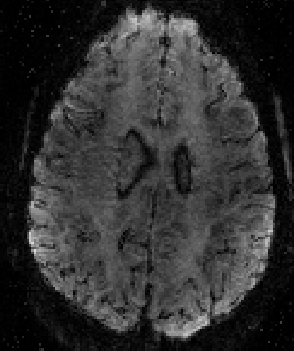

tSNR maps for various ACS schemes: FLASH is better than FLEET. FLEET is often better than single shot. And “segmented” is usually the worst.

FLASH-GRAPPA

FLASH GRAPPA can have a huge impact on signal tSNR. Here an example of segmented vs. FLASH GRAPPA.

In FLASH GRAPPA, the reference lines are acquired without most of the biases of EPI-based reference data. E.g. no distortions, no delays between lines etc.